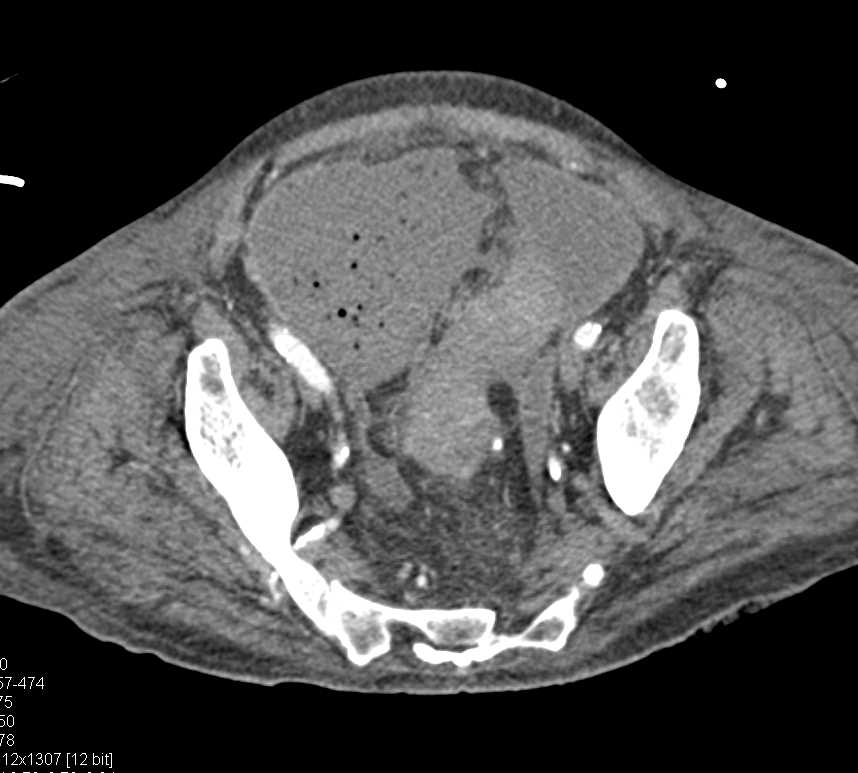

Retroperitoneal Liposarcoma